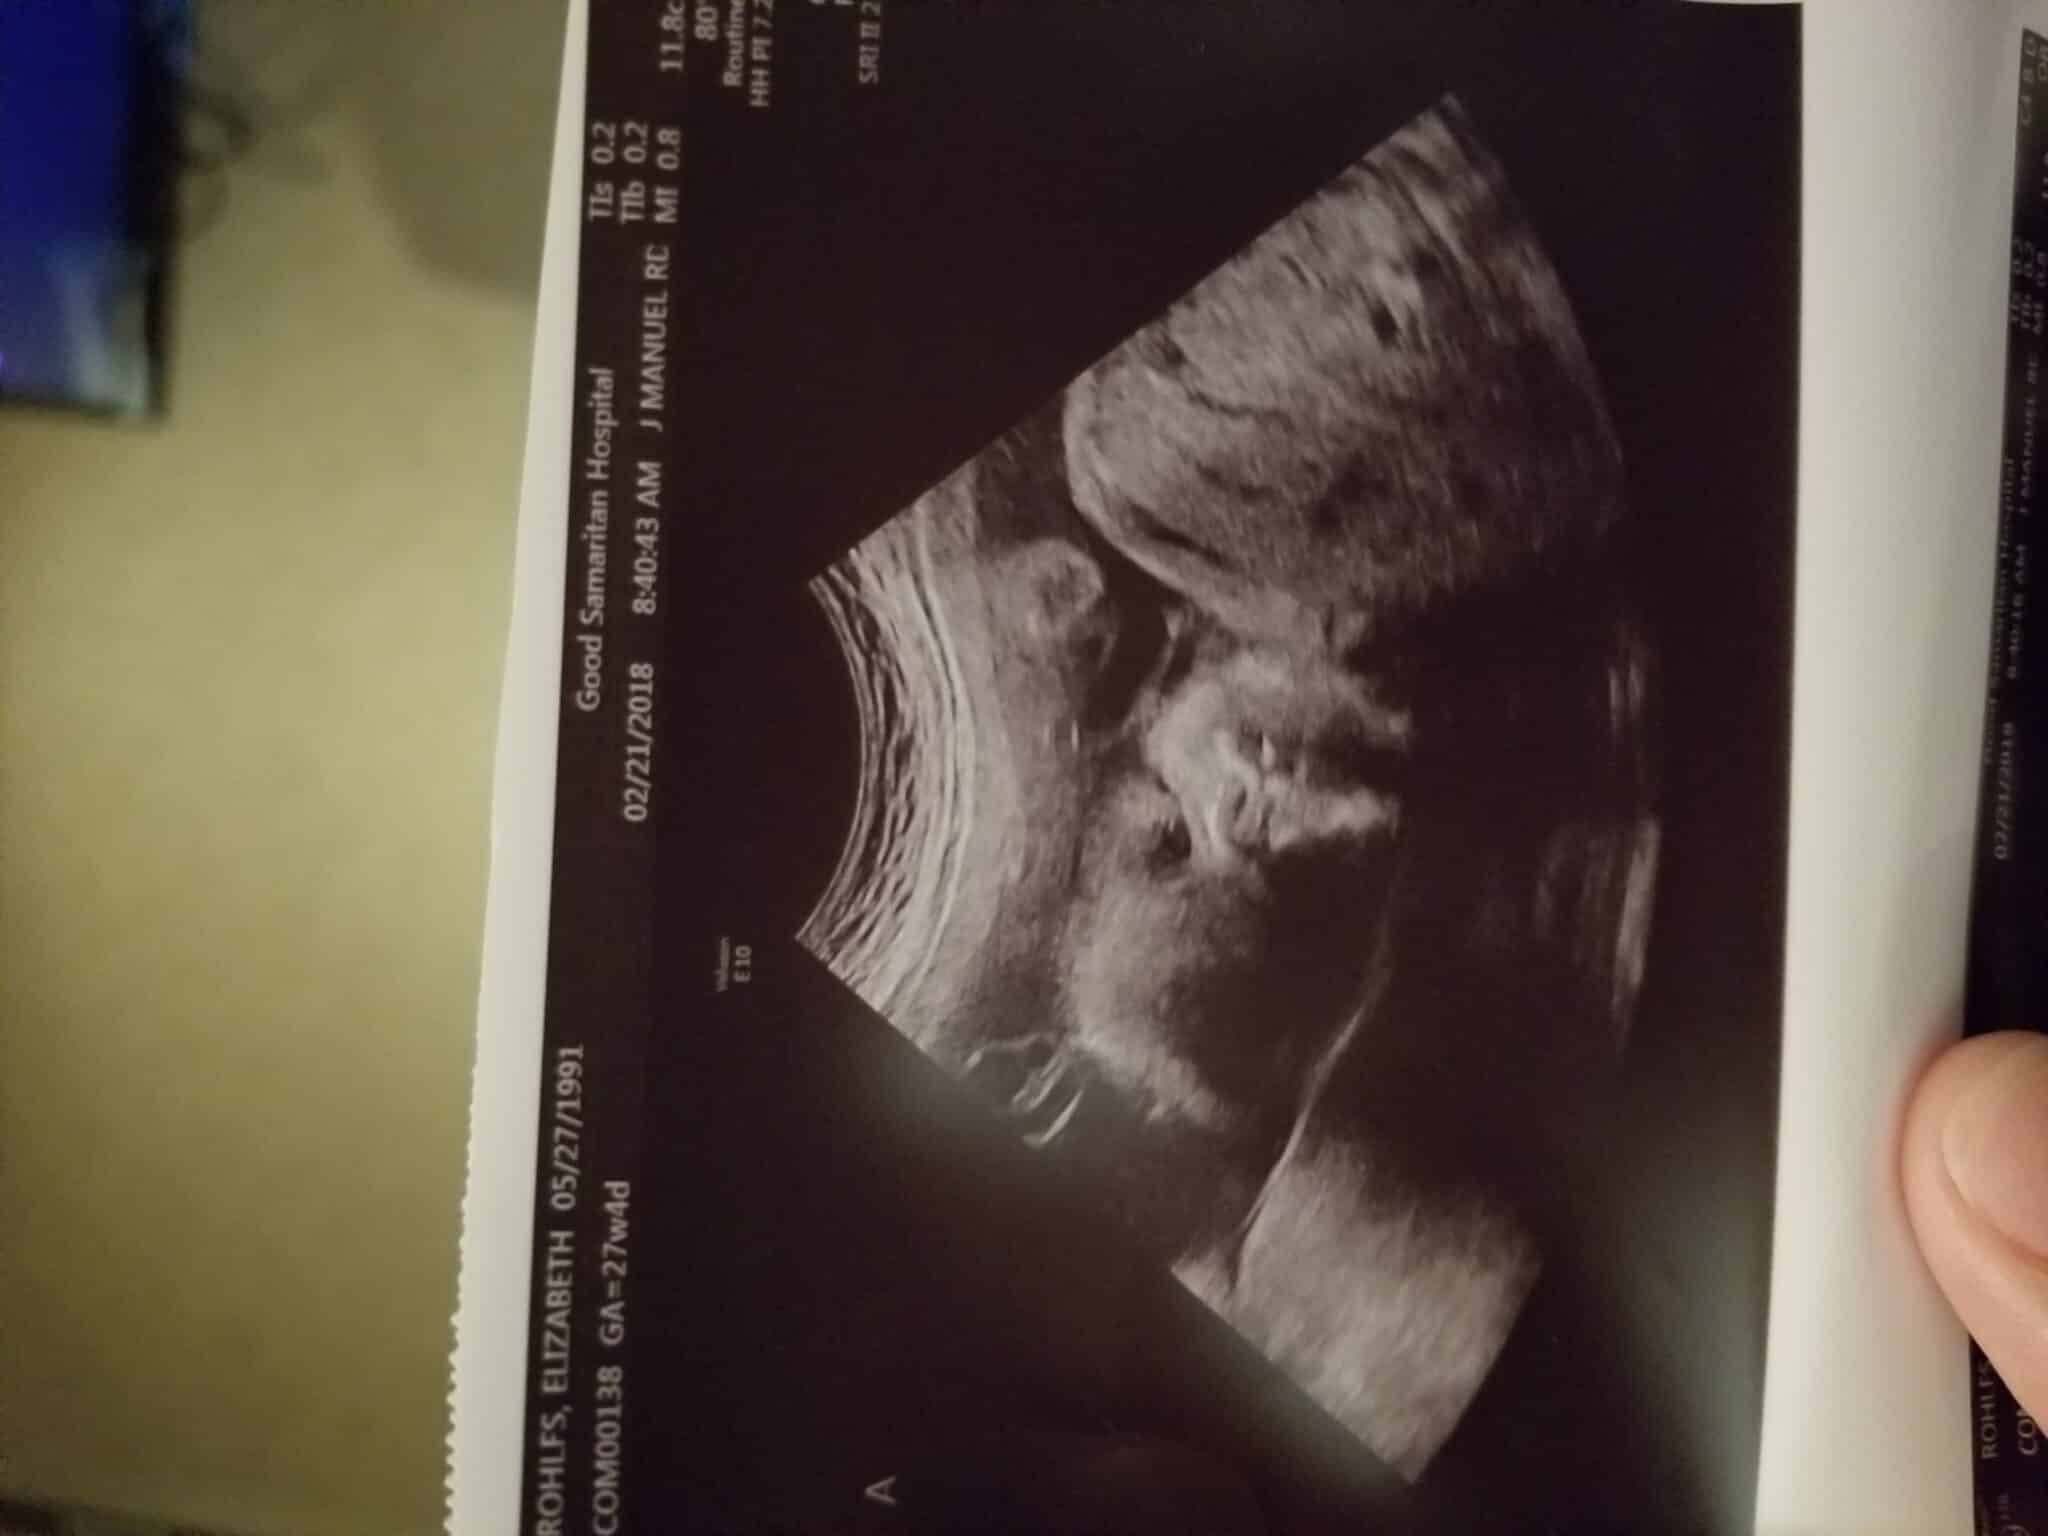

Ultrasound Photos at 27 Weeks Pregnant With Twins